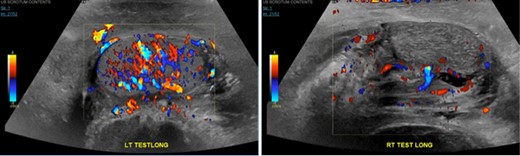

On the following day after the right transfemoral access approach, patient presents to ED with R groin and scrotal pain. On evaluation, severe tenderness on the R groin and scrotum was noted associated with worsening swelling and ecchymosis (Fig. 1). Vitals were within normal limits and initial hemoglobin of 12 g/dl. Ultrasound of the right groin showed a 6.3 × 4.0 × 4.9 cm hematoma (Fig. 2), his duplex ultrasound of bilateral testicle showed diminished blood flow on the right compared to the left (Fig. 3). CT of the pelvis revealed a pseudo-aneurysm on the R groin originating from the common femoral artery (CFA) measuring 2.5 × 1.4 cm and extending into the R inguinal canal, filled with hemorrhage and extension into the R scrotum that measures 13.7 × 6.4 × 6.6 cm (Fig. 4). During his clinical course, he has been hemodynamically stable in spite of drops in daily hemoglobin from 12, 8.9, 6.9, 5.9 g/dl, respectively, requiring two units of blood transfusions on hospital Day 3, and achieving a rise in hemoglobin to 8.6 g/dl. Patient then underwent an ultrasound-guided thrombin injection of the pseudo-aneurysm by the interventional radiologist without any complications and without any evidence of recurrence on ultrasound on the following day. Urology was consulted and offered no urologic interventions as his symptoms were improving. The scrotal and groin hematoma subsequently decreased in size. Patient was discharged on hospital Day 6 with aspirin and Plavix. Patient was followed up in clinic with no complains. On exam, there was a decreasing scrotal and R groin swelling/ecchymosis and improvement of penile swelling.

Right testicle is heterogeneous in texture and demonstrates relatively attenuated vascular flow compared to the left.